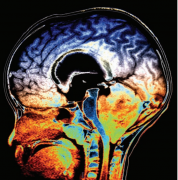

成人脑积水什么情况下需手术?手术方法的选择,需要根据病...